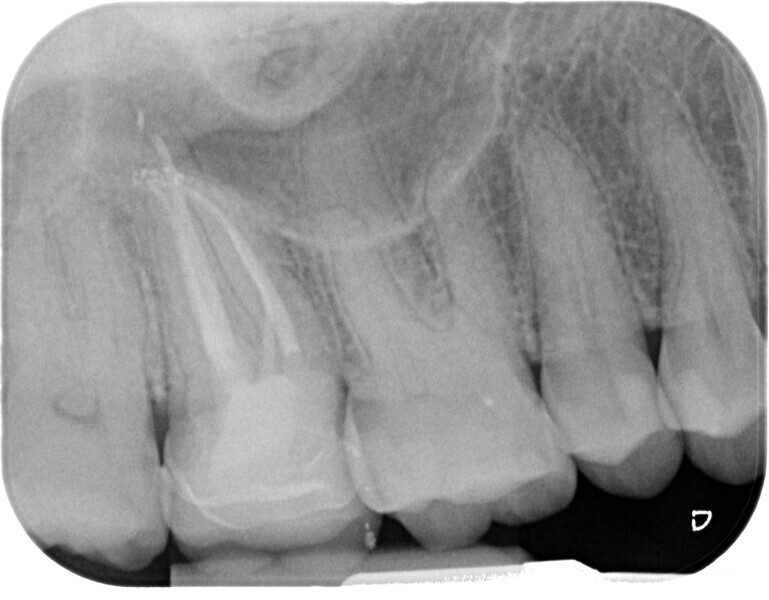

Fig. 13 : Emplacement des mesures effectuées par Deutsch et al.8, 9 sur une molaire inférieure analysée par micro-TDM (avec l’aimable autorisation du Prof. Elio Berutti).

Dans les molaires, la distance entre la pointe d’une cuspide et le plafond de la cavité pulpaire est d’environ 6,3 mm, tandis que dans les prémolaires supérieures, elle est de 6,94 mm. La cavité pulpaire a une hauteur d’environ 1,5 à 2 mm et la distance moyenne entre le plancher de la cavité et la furcation est d’environ 3 mm (Tableau 1) (Fig. 13).